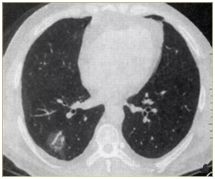

肺部小結(jié)節(jié)通常是指影像檢查(X線或者CT)中發(fā)現(xiàn)的直徑≤2cm的類圓形病灶,≤3cm的稱為結(jié)節(jié),>3cm的稱為腫塊。

也有學(xué)者認(rèn)為,分得太細(xì)并無意義,例如2.2cm的結(jié)節(jié)與1.9cm的小結(jié)節(jié),臨床上并沒有本質(zhì)的區(qū)別。在這里我們統(tǒng)一把≤3cm的結(jié)節(jié)統(tǒng)稱為肺部小結(jié)節(jié),在肺部小結(jié)節(jié)中,60%—70%為良性結(jié)節(jié),30%—40%的結(jié)節(jié)方為惡性結(jié)節(jié),所以,發(fā)現(xiàn)肺部小結(jié)節(jié)切勿驚慌。

我們常看到的影像學(xué)描述中的“磨玻璃結(jié)節(jié)(GGO)”,其中一部分是非典型腺瘤樣增生(AAH)或原位腺癌(AIS),結(jié)節(jié)內(nèi)部的實(shí)變與生長速度的加快(范圍變大)常意味病變性質(zhì)的轉(zhuǎn)變,可以逐步演變?yōu)槲⒔櫹侔∕IS)、浸潤性腺癌(IAC)。